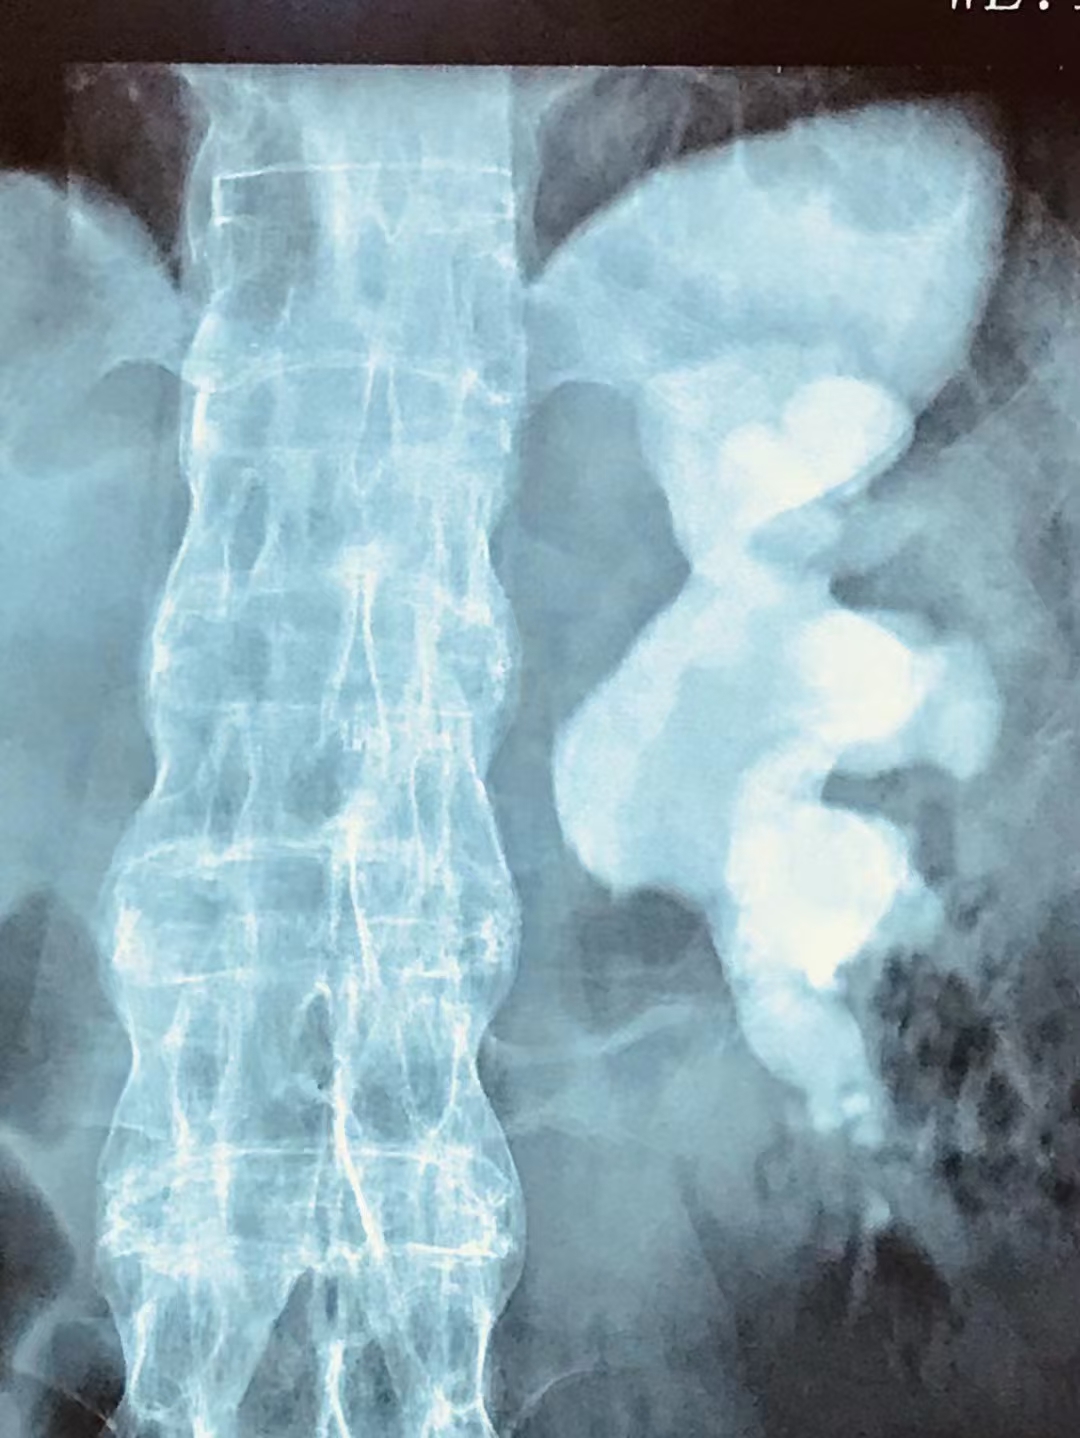

无论是由结石梗阻所引发的肾积水,还是随着病程延长而持续增大、侵占肾内空间所形成的铸型结石,最终都会带来一个共同的后果,那就是:肾实质会由于受到挤压而不断变薄,进而引起肾脏萎缩、肾功能不全等。